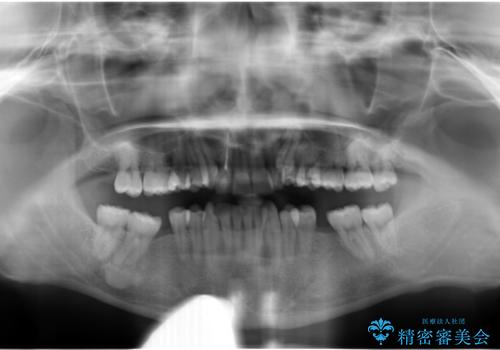

下の歯がないところに、奥歯が倒れこんでいたため、矯正治療で倒れこんだ歯を起こして、インプラントを植立しました。

上の前歯が下の前歯に大きく重なっており、過蓋咬合を呈していました。

上顎の小臼歯2本、下顎の親知らずを抜歯しています。